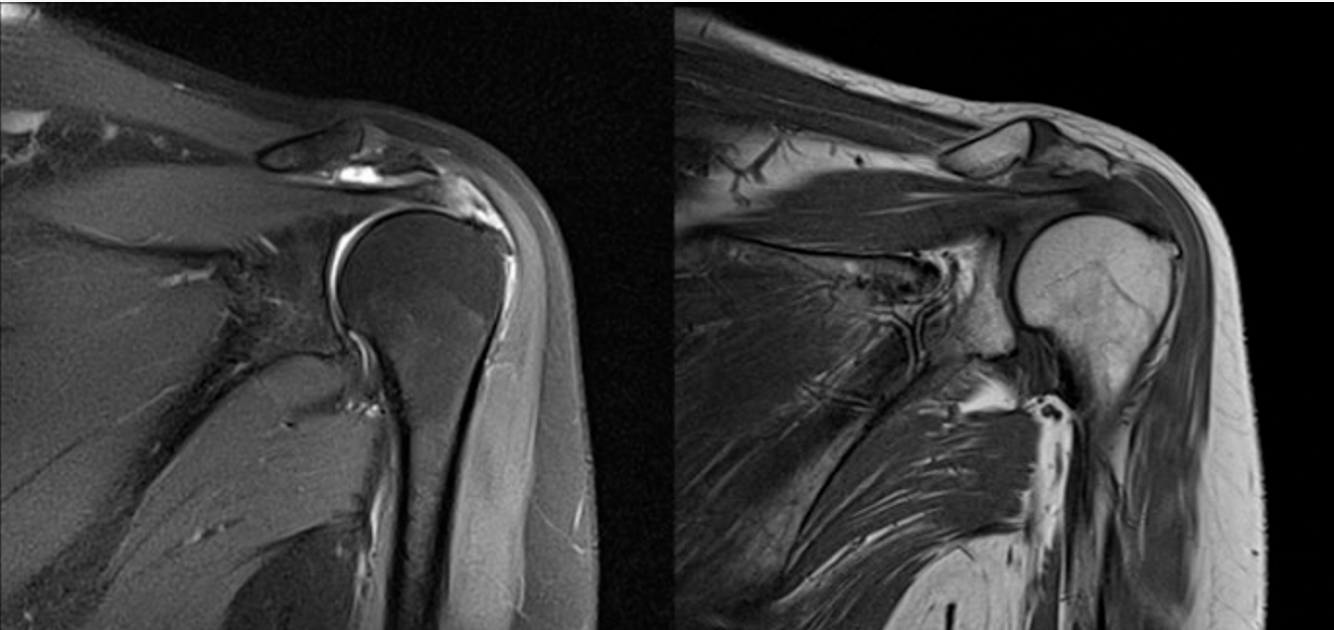

(4)MRI:行MRI检查出现肩关节韧带损伤、肿胀、撕裂可确诊;